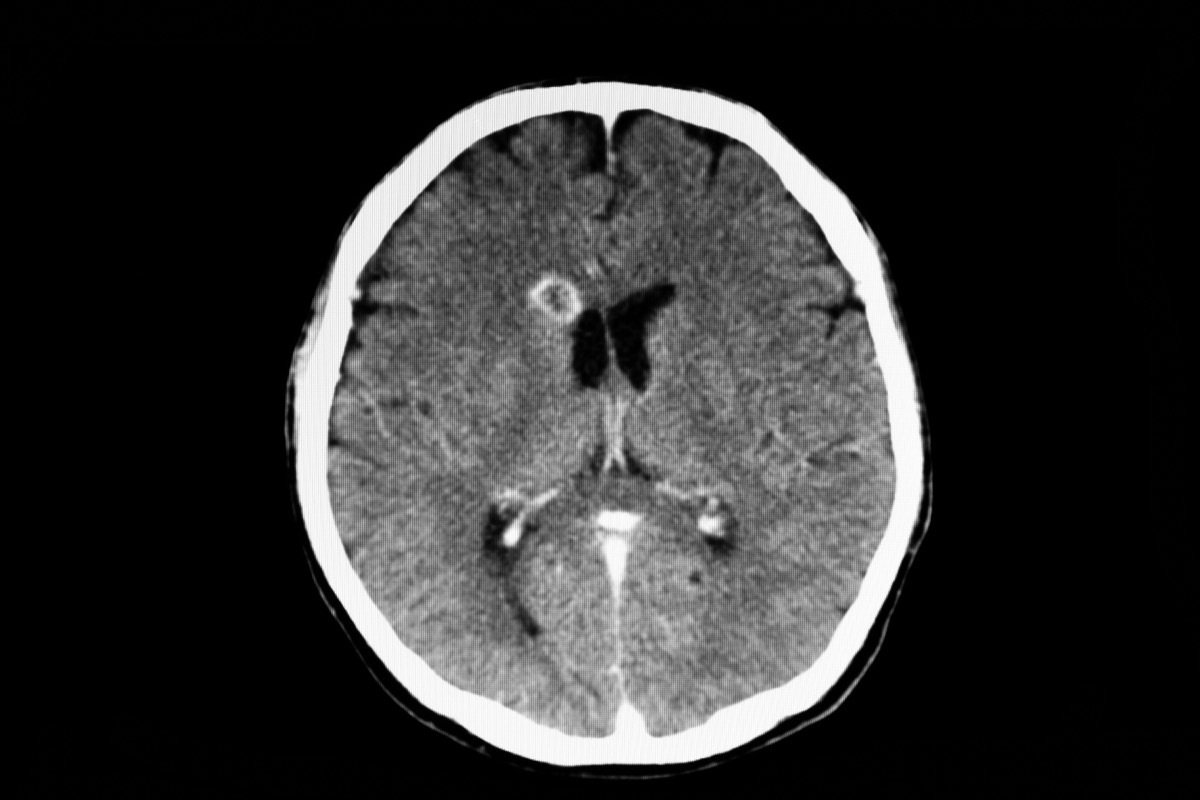

Eine andere parasitäre Infektion, Cysticercose, wird "durch Larvenzysten von verursachtDas Bandwurm Taenia Solium"Sagt die CDC." Diese Larvenzysten infizieren Gehirn, Muskeln oder anderes Gewebe und sind eine Hauptursache für Anfälle für Erwachsene in den meisten Ländern mit niedrigem Einkommen. "

Die Infektion kann zu Zysten führen, die in verschiedenen Bereichen des Körpers auftreten, einschließlich Muskeln, Augen und Gehirn. "Symptome, die durch die Zysten verursacht werden, hängen von Ort, Größe, Anzahl und Stadium der Zysten ab", sagt die CDC.